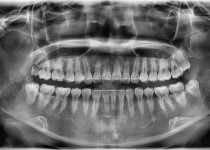

만 82세 하악 풀아치, 상악 임플란트(일…